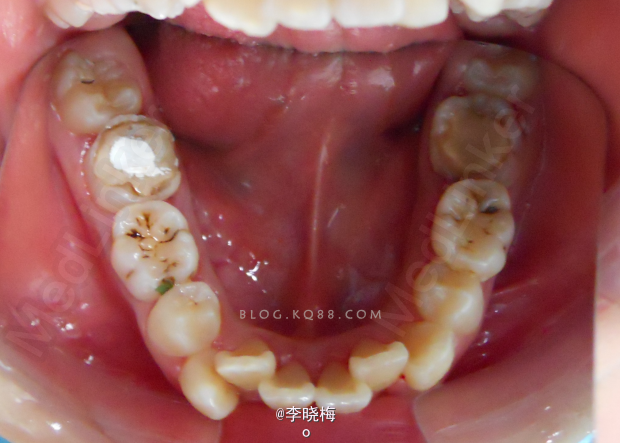

一例前牙Ⅲ度深覆盖的矫治

患者女,14岁,因“上牙前突影响面容”要求矫治,混合牙列,覆盖较大,9毫米,上颌两个门牙完全在牙弓弧度外,微笑时露龈,最棘手的是四个第一磨牙均大面积龋坏,我先将龋坏的磨牙根管治疗,桩核冠修复,拔除双侧上4及下颌Ⅴ,上颌加强支抗后用片段弓拉上颌3,后拔除双侧下颌4,经过一年多的矫治,解除了拥挤,内收了上下前牙,建立了正常的覆颌覆盖。(来源于网络)